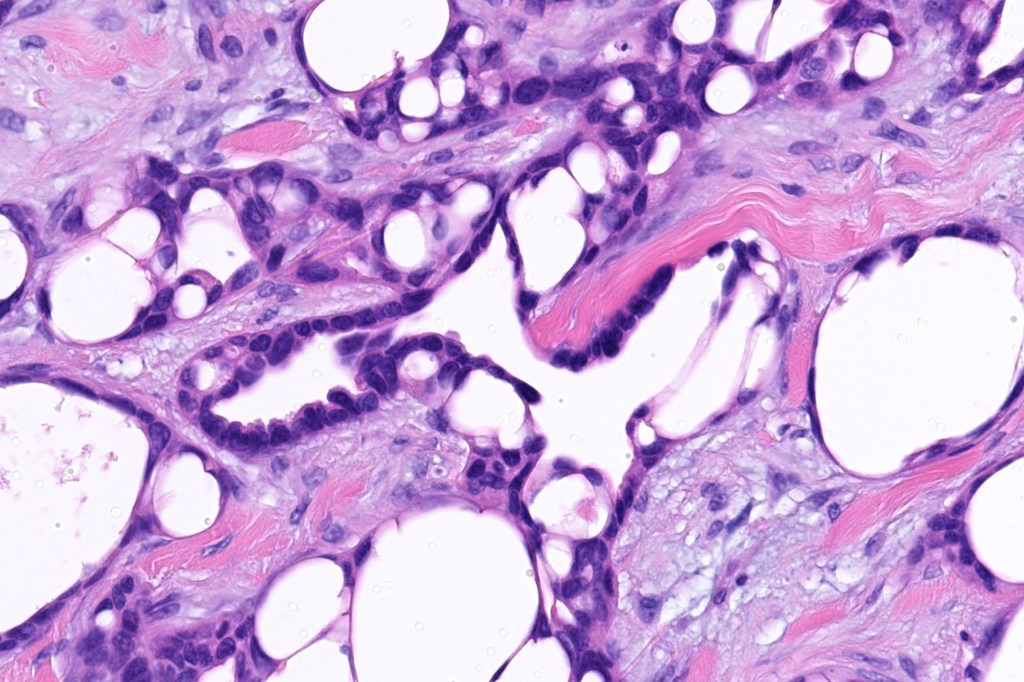

Histological features

•Generally circumscribed nodules/cysts

•Interconnecting epithelial strands giving rise to the cribriform growth pattern

•Ductal differentiation

•Hyperchromatic nuclei with variable pleomorphism

•Mitoses sparse or absent

•Focal decapitation secretion and presence of more typical apocrine carcinoma-like nests